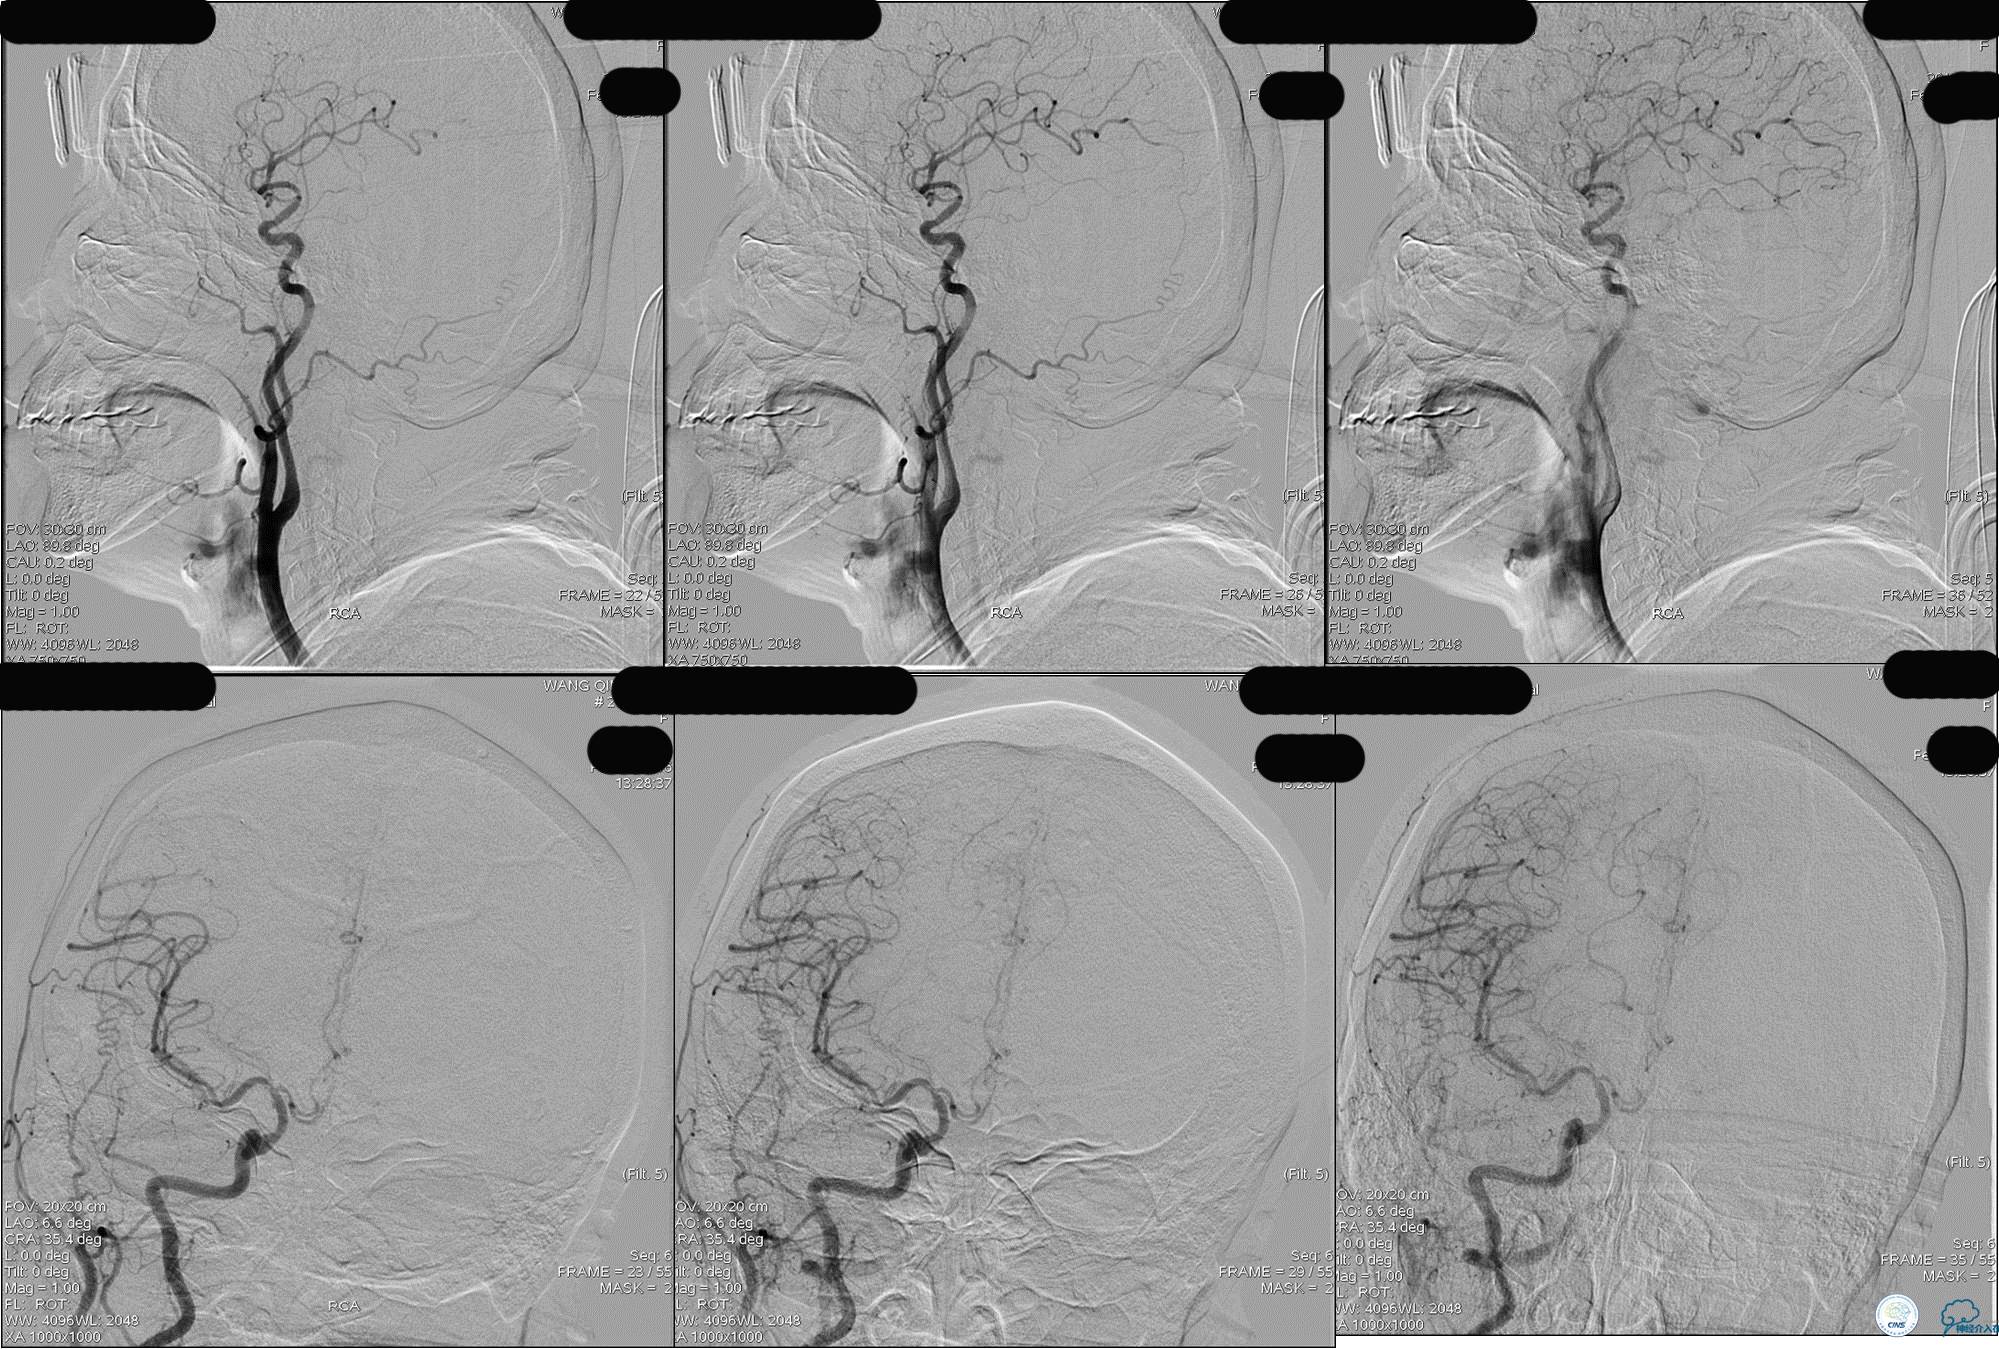

》DSA资料(左侧椎动脉)

》DSA资料(右侧椎动脉)

》DSA资料(经桡动脉,5F导引导管)

》DSA资料(前2次取栓,未取出,soli 4-20)

》DSA资料(第3次取栓)

第3次取出血栓

》DSA资料(第3次取栓后,发病10h)

》DSA资料(观察30min后,左椎造影)